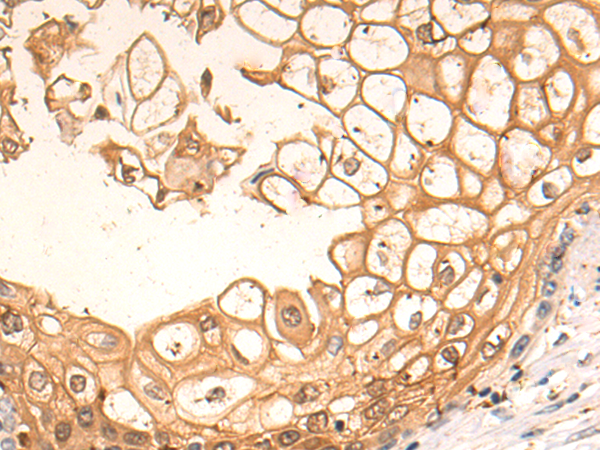

ELISA, IHC

IHC positive control:

Human brain

IHC Recommend dilution:

25-100